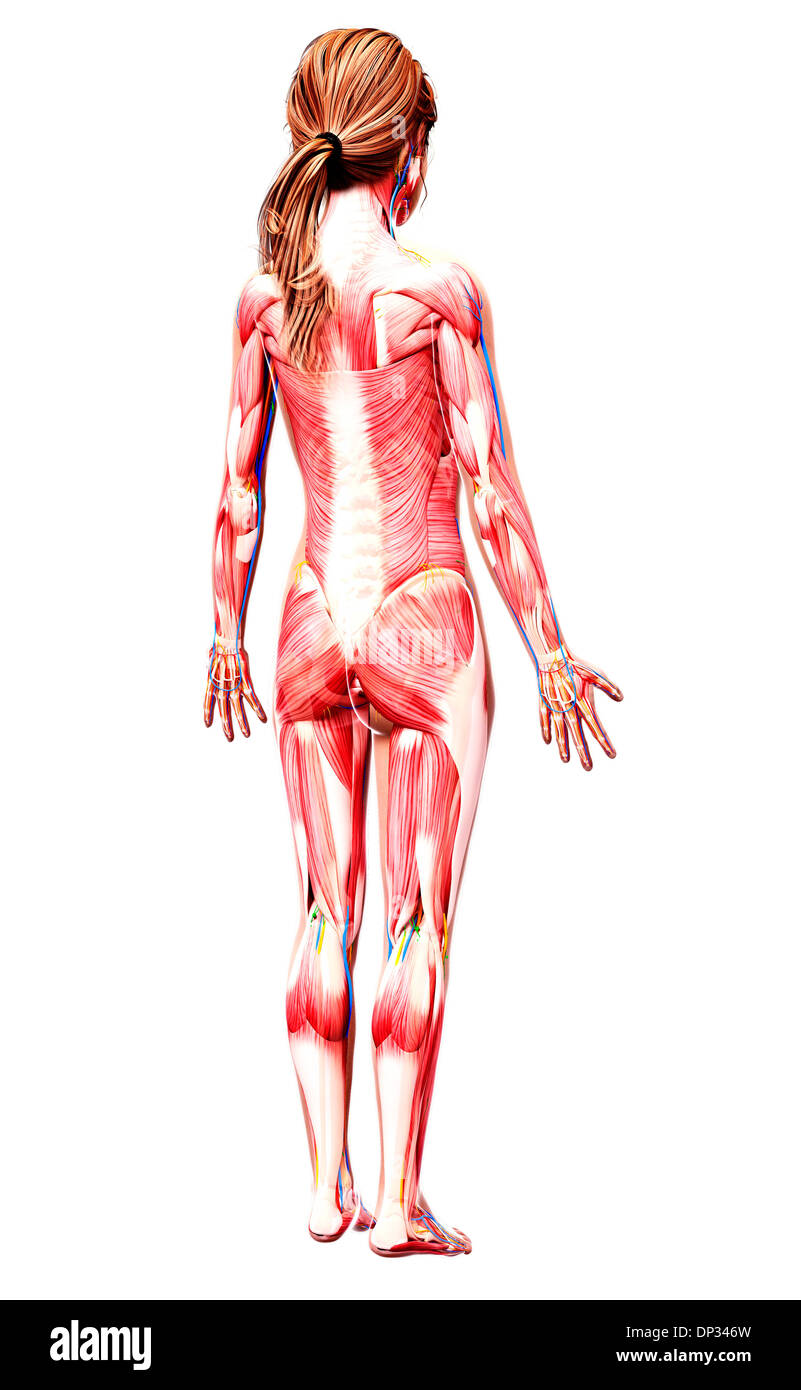

Human Anatomy, artwork Banque D'Imageshttps://www.alamyimages.fr/image-license-details/?v=1https://www.alamyimages.fr/human-anatomy-artwork-image65239446.html

Human Anatomy, artwork Banque D'Imageshttps://www.alamyimages.fr/image-license-details/?v=1https://www.alamyimages.fr/human-anatomy-artwork-image65239446.htmlRFDP3WG6–Human Anatomy, artwork